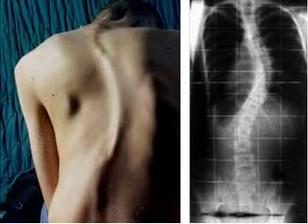

La escoliosis es la curva lateral de la columna vertebral, anormal y progresiva de inicio y evolución silenciosa, asociada a la rotación de los cuerpos vertebrales y a la alteración estructural de las vértebras. La escoliosis ofrece unos síntomas muy evidentes y visibles y con una exploración rutinaria en tu médico de cabecera puede ser detectable, el dolor de espalda y problemas respiratorios o cardiacos, sólo aparecen en casos muy avanzados.

El principal síntoma de la escoliosis es una curva en la columna con forma de C (o S cuando se combina con la escoliosis dorsal en la parte superior de la columna) en lugar de una línea recta desde el cuello hasta la cadera. La curva puede ser notoria durante una radiografía de tórax para la determinar una lesión o infección pulmonar o puede aparecer en una prueba de flexibilidad.